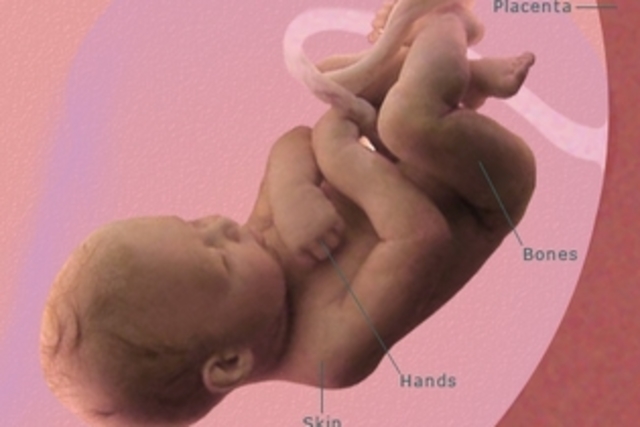

- Su piel sigue siendo tan sumamente fina que a través de ella se pueden ver algunos de los órganos internos y los vasos sanguíneos.

- Su cabeza ya está bastante erguida. Aunque los párpados siguen cerrados el globo ocular se mueve. Su piel sigue siendo muy fina y empiezan a formarse el sentido del tacto.

La piel es de un color rojizo porque todavía no ha acumulado suficiente grasa debajo de ella, aunque se empieza a engrosar y ya cuenta con sus respectivas capas.

La formación de los huesos sigue su desarrollo. El cartílago poco a poco se va osificando, proceso que comienza desde el centro del hueso y progresa hacia los extremos del mismo.

La piel ya no es traslúcida en la semana 23 de embarazo, sino rojiza y arrugada y comienza a cubrirse de vérnix caseoso, una capa de grasa producida por las glándulas sebáceas fetales.Esa capa le protegerá durante toda la gestación y suele nacer con ella.